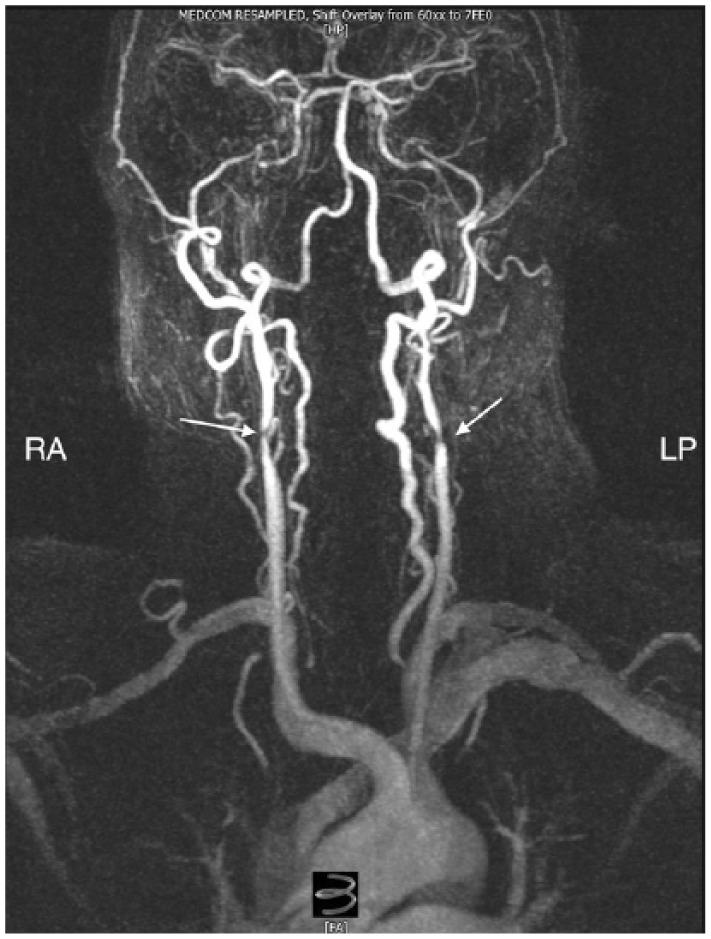

Carotid stump syndrome is defined as the persistence of retinal or cerebral ischaemic events with complete occlusion of the ipsilateral internal carotid artery. The aim of this retrospective cases series was to assess the outcomes for patients with carotid stump syndrome managed with surgical intervention. A series of 11 cases of carotid stump syndrome in nine patients presented to our tertiary vascular centre from October 2004 to February 2016. Indications for intervention were amaurosis fugax, transient ischaemic attacks and stroke. In total, 11 procedures were performed on nine patients including carotid angioplasty and stenting or carotid endarterectomy with patching. The mean follow-up period was 56.6 months. One patient suffered a myocardial infarction 30 days, post-operatively, and one patient was lost to follow-up. In the remaining seven patients, there was a complete resolution of symptoms. There were no incidents of death, stroke, cranial nerve injury, wound haematoma or procedural bleeding. Surgical exclusion of carotid stumps combined with dual antiplatelet agents was found to be a safe and effective treatment method for carotid stump syndrome.

颈动脉残端综合征的定义为同侧颈内动脉完全闭塞时视网膜或脑部缺血事件持续存在。本回顾性病例系列的目的是评估接受手术干预治疗的颈动脉残端综合征患者的治疗效果。2004年10月至2016年2月期间,9例患者中的11例颈动脉残端综合征病例被送至我们的三级血管中心。干预指征为一过性黑矇、短暂性脑缺血发作和中风。总共对9例患者进行了11次手术,包括颈动脉血管成形术和支架置入术或颈动脉内膜切除术加修补术。平均随访期为56.6个月。1例患者术后30天发生心肌梗死,1例患者失访。其余7例患者症状完全缓解。未发生死亡、中风、颅神经损伤、伤口血肿或手术出血事件。发现手术切除颈动脉残端联合双联抗血小板药物是治疗颈动脉残端综合征的一种安全有效的方法。